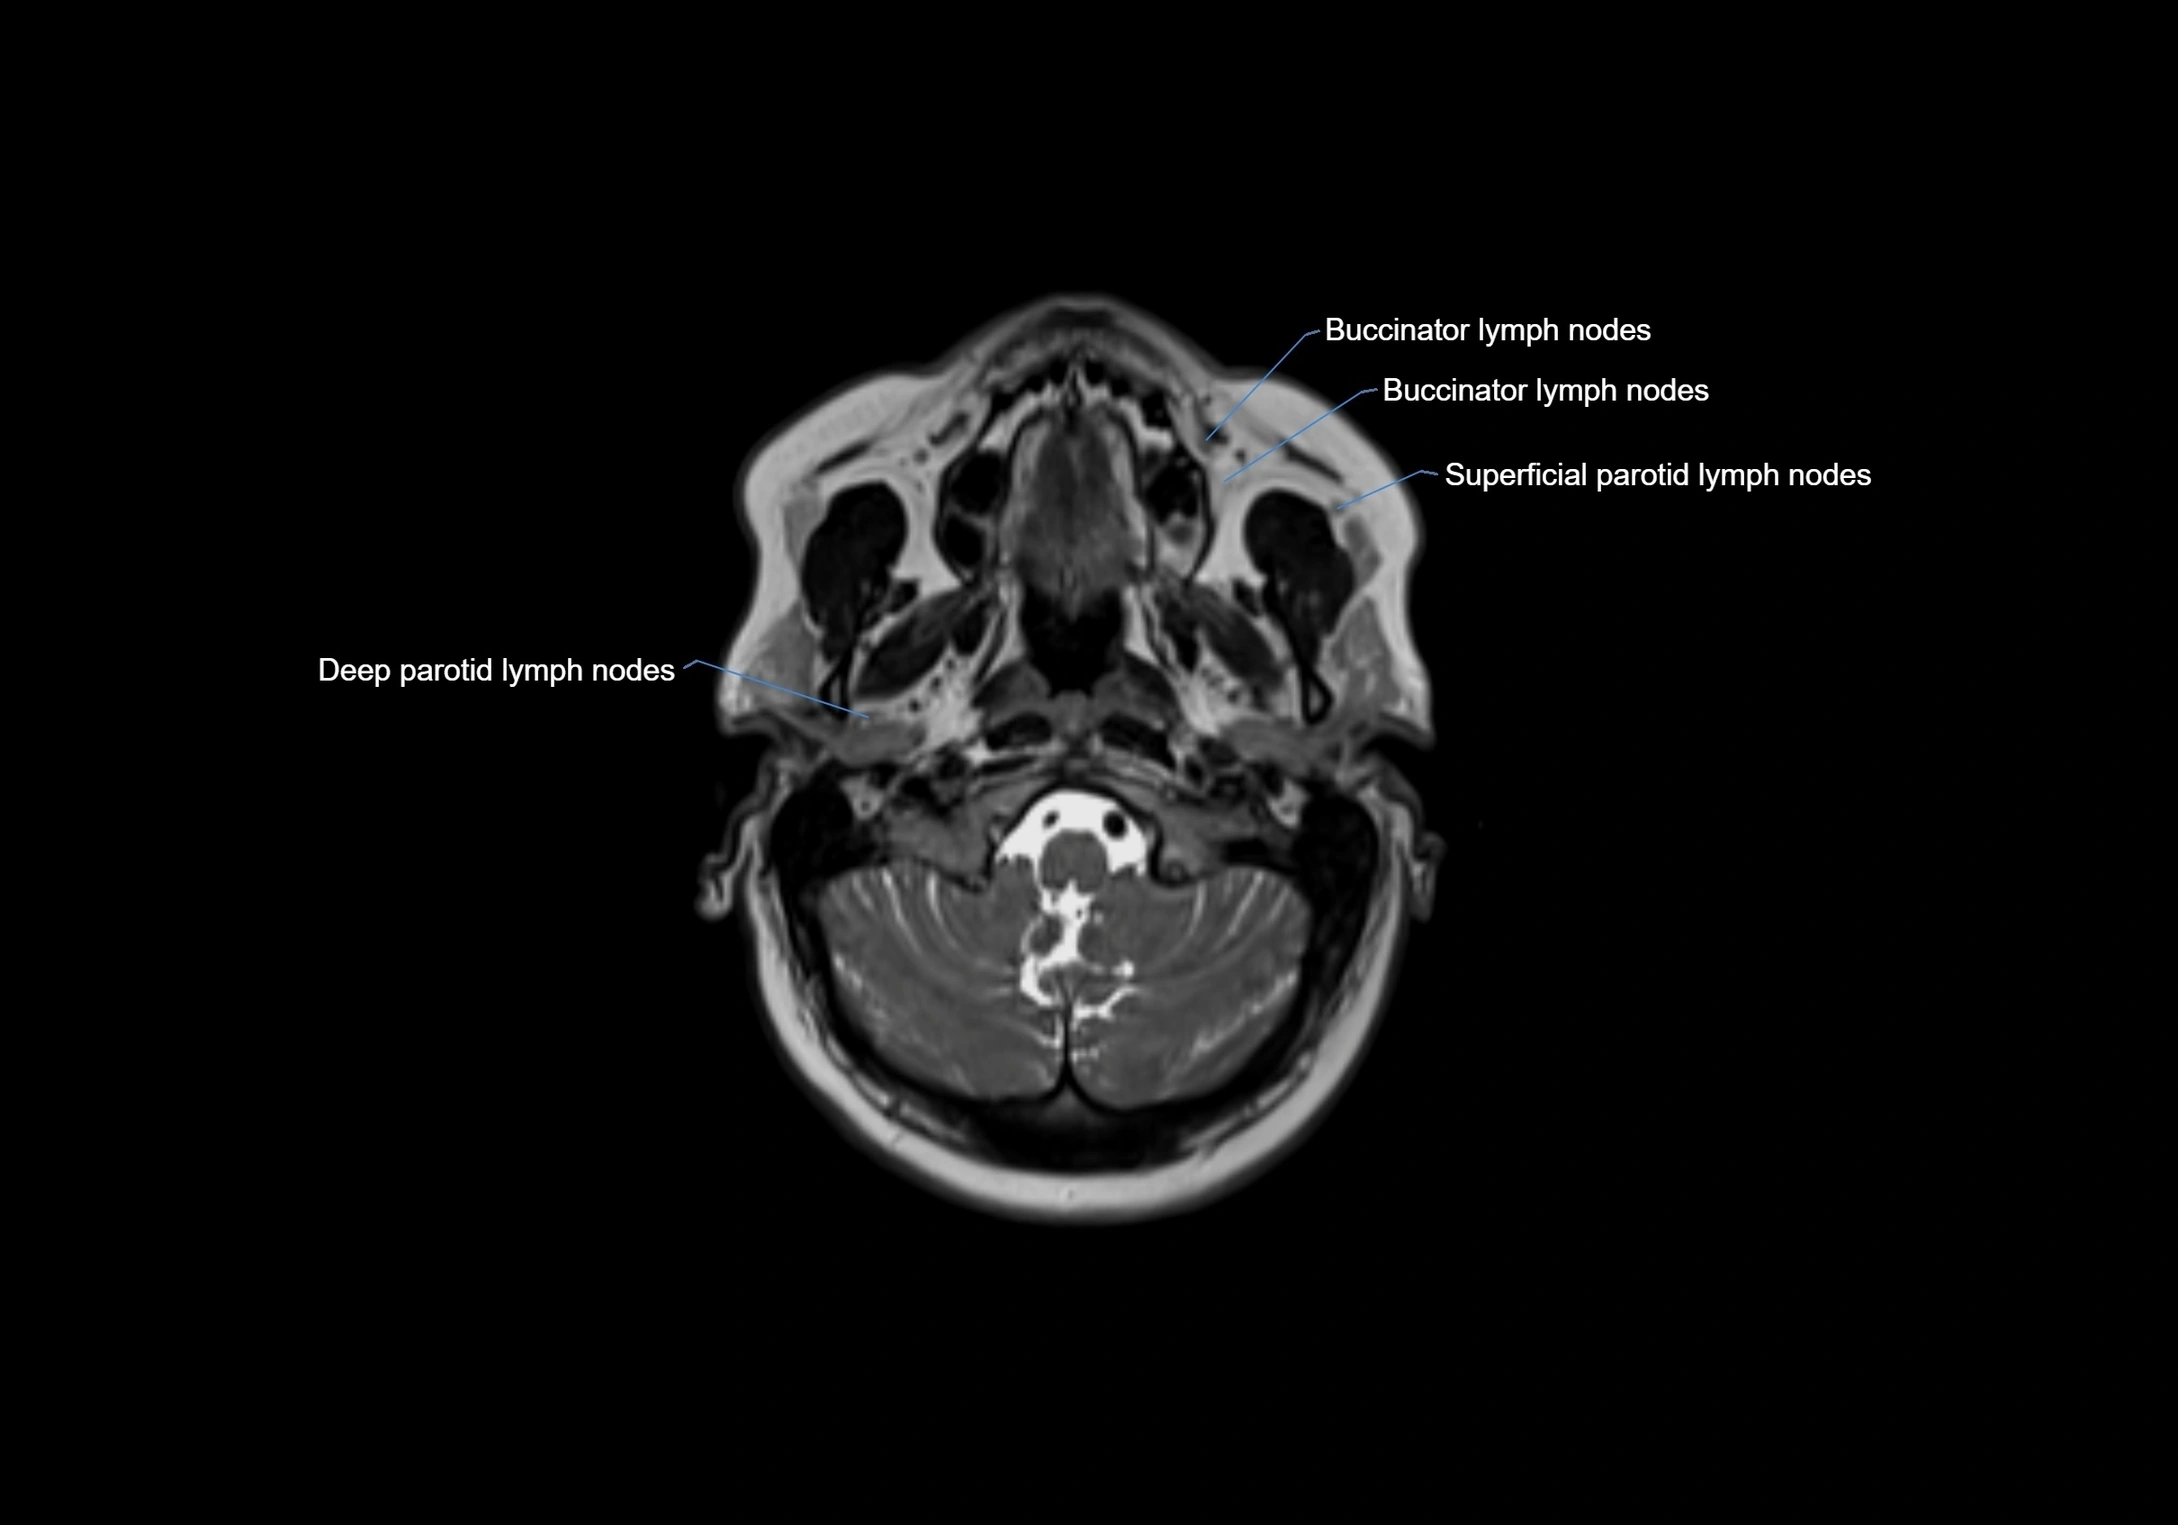

Location

• Found along primary lymph node chains, including preauricular, submandibular, parotid, and occipital regions

• Embedded in subcutaneous fat or superficial fascia, often lateral or posterior to primary nodes

• Variable in number; may occur unilaterally or bilaterally, depending on individual anatomy

MRI Appearance

T1 Post-Contrast (Gadolinium-enhanced):

• Normal nodes may show mild, homogeneous enhancement

• Inflamed or metastatic nodes demonstrate marked homogeneous or heterogeneous enhancement, highlighting the cortex and fatty hilum

• Post-contrast imaging helps detect early metastasis, infection, or inflammatory changes

MRI images

image